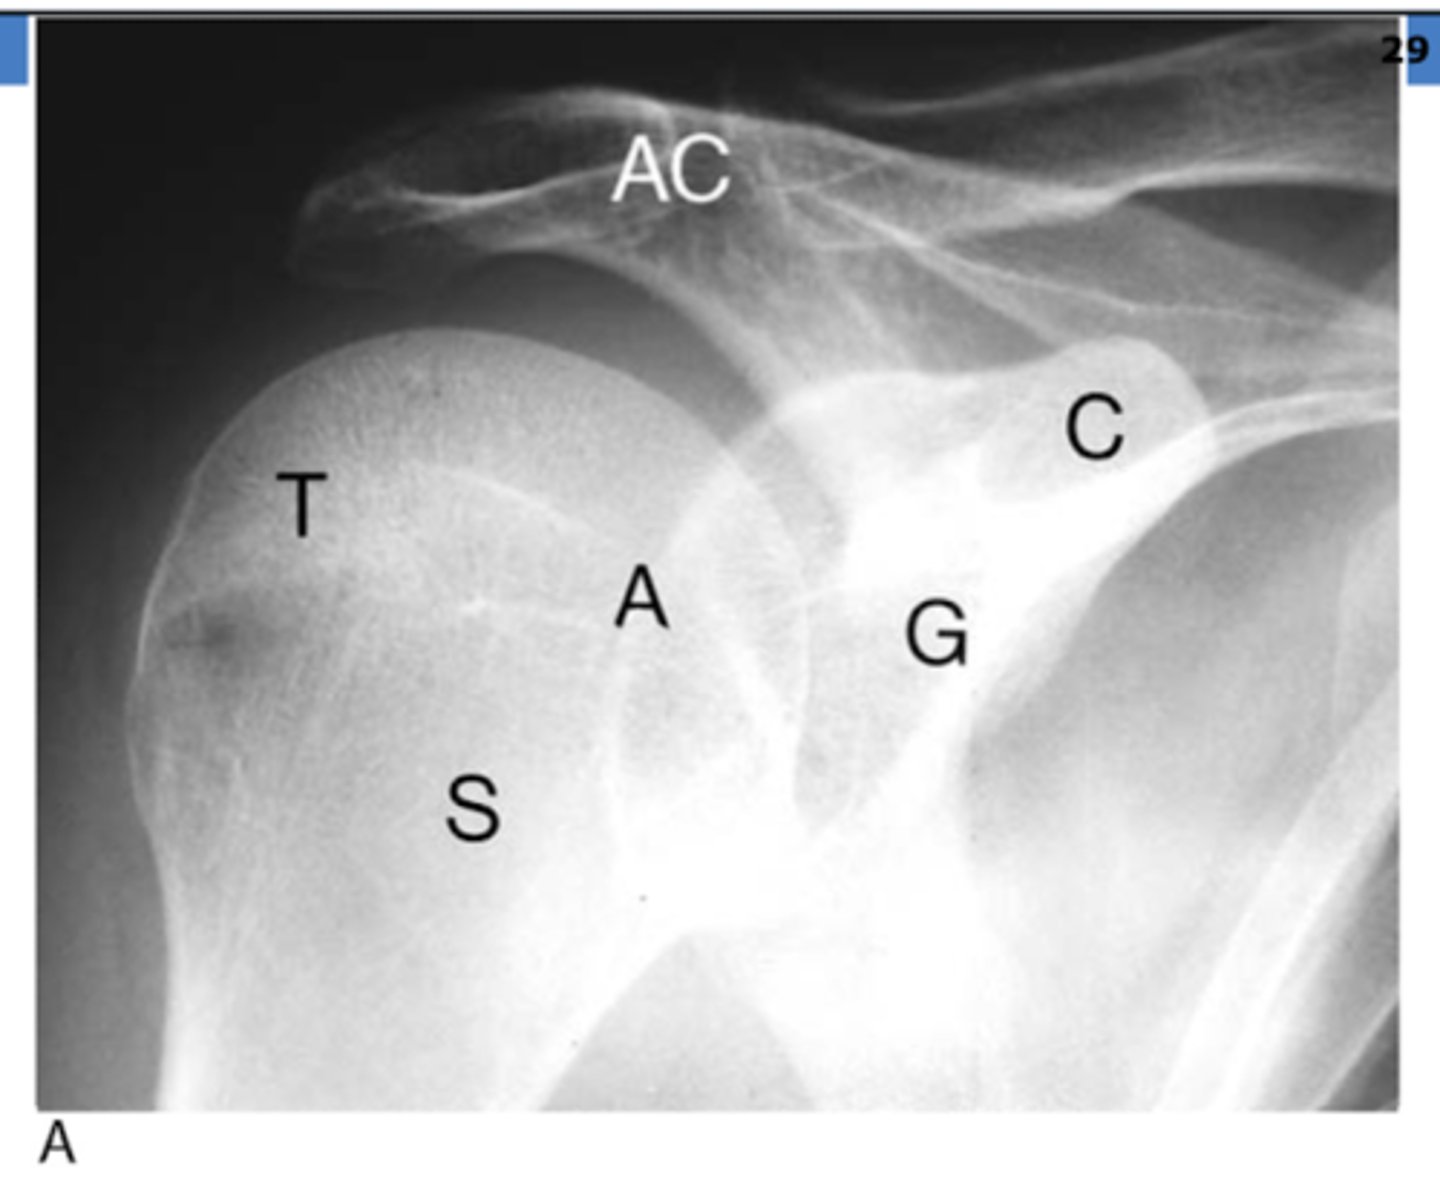

REVIEW: Shoulder XR (AP view)

REVIEW: Shoulder XR (AP view - II)

T → greater tuberosity

S → surgical neck of humerus

A → anatomical neck of humerus

G → glenoid fossa

C → coracoid process

AC → acromion process